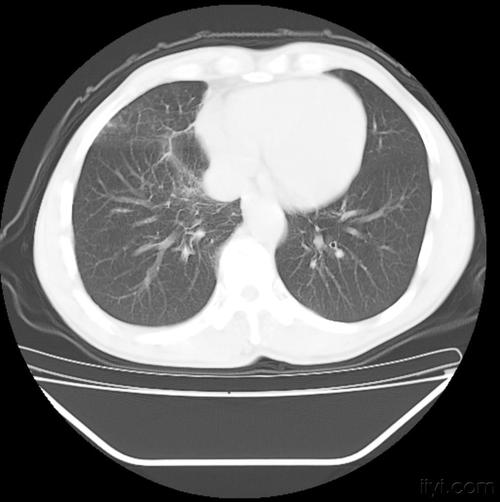

胸部ct清晰显示肺癌病灶的各种影像特征